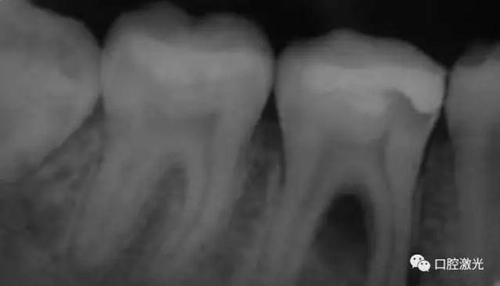

11、21 治療前